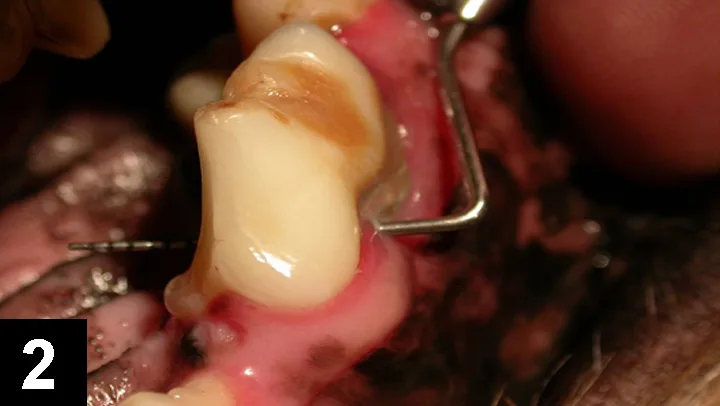

A close-up view of a dog's mouth shows a surgical site with exposed tissue and blood following a dental procedure. The image highlights the upper canine teeth and the surrounding gingival area, indicating potential periodontal disease or extraction.

Figure 3: Maxillary left fourth premolar (#208) in a dog: This patient had slight to moderate gingival recession, minimal periodontal pocketing, and approximately 20% alveolar bone loss. Regardless, there is complete furcation exposure (level II), which requires periodontal flap surgery (or extraction) to remove the infection.